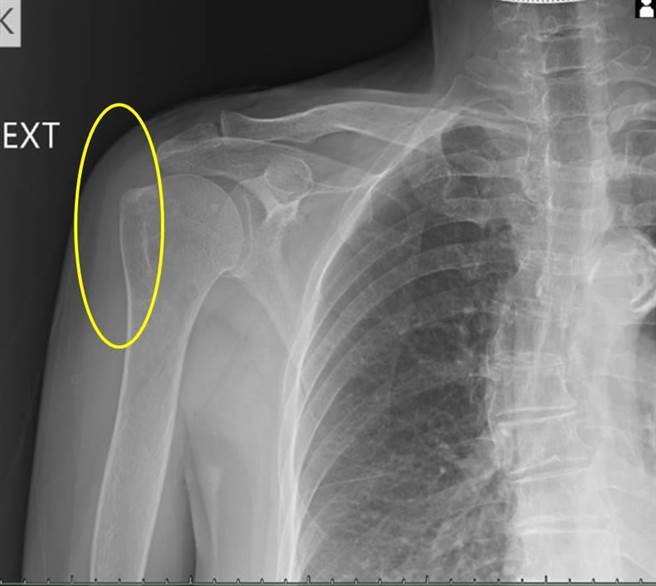

今年67岁的陈女士肩膀经常疼痛,今年1月到丰原医院挂復健科门诊,理学检查发现手臂上抬与内转时会因严重疼痛而无力,当天安排X光检查后,发现除有旋转肌肌腱炎外,还出现严重钙化,就是肩关节钙化性肌腱炎;建议她除做一般常规復健外,再安排3次的自费震波治疗,一个月后追踪照X光片发现钙化点完全消失,肩关节疼痛与功能都得到大幅度的改善。

丰原医院復健科医师张宪伯说,体外震波对钙化性肌腱炎是种非常有效的治疗方式,根据研究透过3次震波并追踪3个月后,钙化点多能显着变小,甚至有36%病人钙化点可在震波3个月后完全消失;相较于没有復健需要经过3-10年才有1/3的病人会慢慢吸收,打震波的效果快而显着。